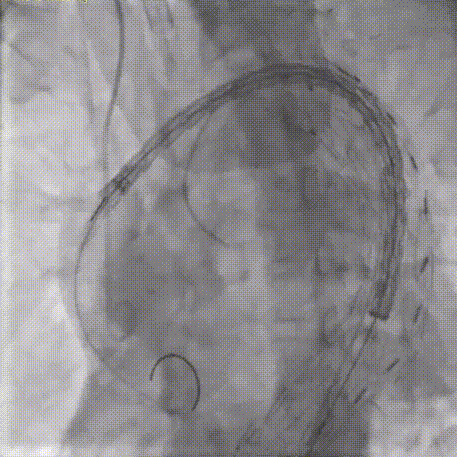

CADS第一步释放,支架从近段向远端打开,释放至50%直径,造影确认调整支架近端位置,精准定位于INA远端。

CADS第二步释放,支架从远端向近端打开,释放至全直径;随后可以选择性调整近端成角,优化小弯侧贴壁。

9.经MPA导管送入申淇弹簧圈3条和2盒纤维蛋白粘合剂至主动脉弓瘤体内,经TRG导管送入COOK弹簧圈3条栓塞左锁骨下动脉根部。整体造影见胸主动脉支架贴壁良好,未见内漏,双侧颈总动脉、椎动脉、腋动脉显影良好,未受影响。